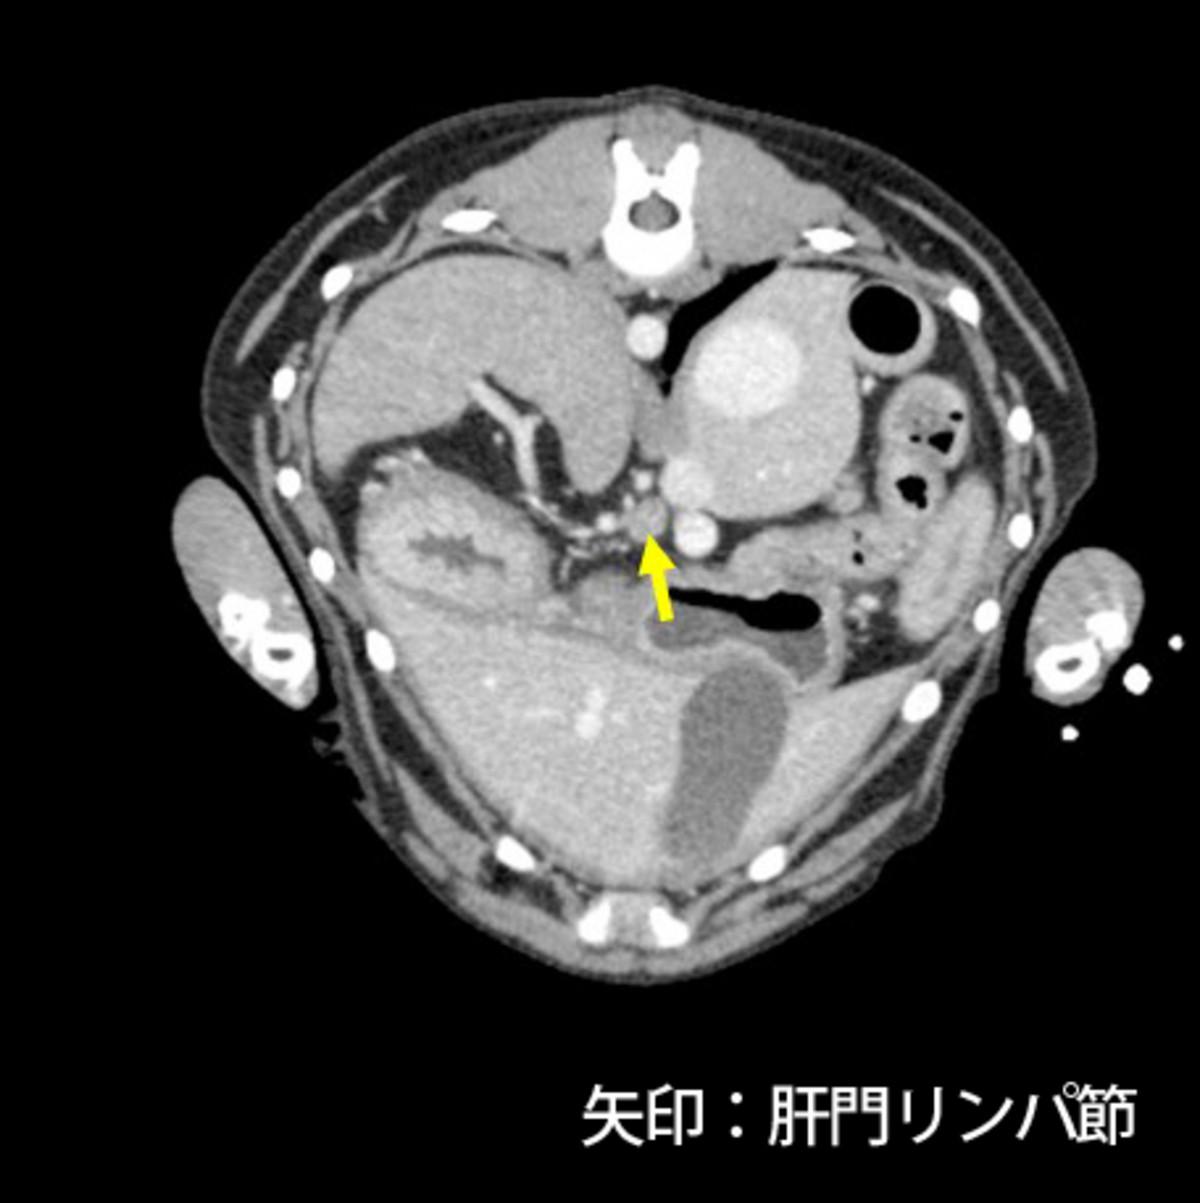

症例はバセンジー、去勢雄、11歳8ヵ月齢、10.5kgです。当院初診の一月前にふらつきを認め近医を受診し、低血糖(38mg/dL)、インスリン高値が認められたためインスリノーマと仮診断され、少量頻回の食事と糖液の投与により一般状態を維持していました。初診時の血液検査では血糖値は正常であり、CT検査にて膵臓右葉尾側に腫瘤(15×10×10mm)、肝臓外側左葉の腫瘤(5mm大×2)、肝門リンパ節腫大(12×10×6mm、15×9×7mm)が認められました(図1)。肝臓への転移が疑われるため、根治は難しい可能性が高いものの臨床症状およびQOLの改善を目的とした手術が予定されました。

図1.CT検査にて膵臓腫瘤(図1-1)、肝門リンパ節腫大(図1-2、1-3)を認めた